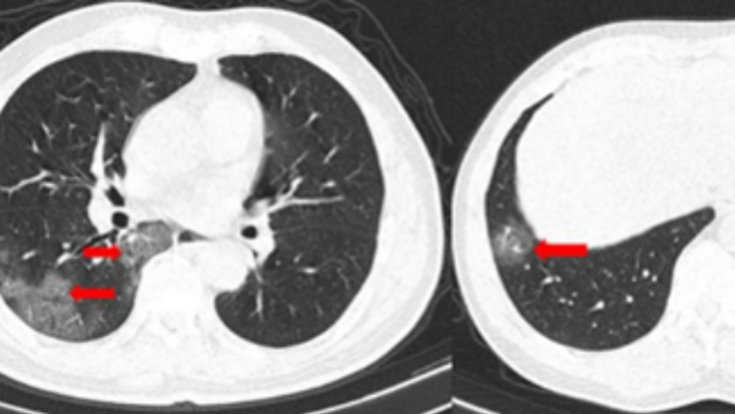

新型コロナウイルス感染症における胸部ct像の特徴